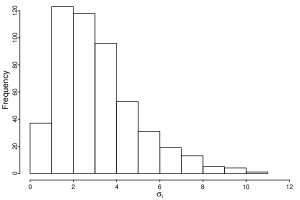

Figure 2 displays the histogram for the posterior estimates of the within-individual standard deviation, , which are considerably heterogeneous and right skewed. This fact is one more reason supporting the assumption of heterogeneous variance which led us to to consider a dispersion model when analysing the CD4 repeated measures. These estimates contrast with the common value, , for the model where a structure for the dispersion is not considered.